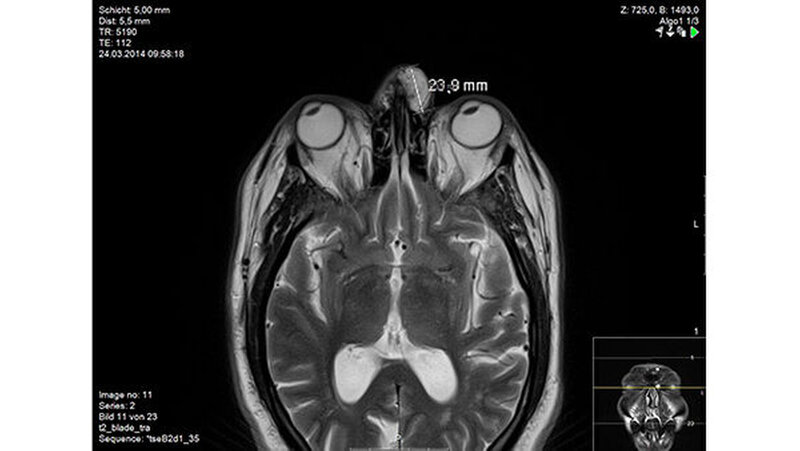

In der Magnetresonanztomografie des Gesichtsschädels zeigte sich eine etwas lobuliert imponierende und signalreiche Läsion frontonasal subkutan links. Der Tumor war mittellinienüberschreitend und zeigte ein koronares Ausmaß von 20 x 40 Millimetern sowie ein transversales Ausmaß bis zu maximal 24 Millimeter (Abbildungen 2 und 3 ).

Es lag ein intensives, jedoch etwas heterogenes Kontrastmittel-Enhancement vor. Die Drainage des Prozesses erfolgte über ein Galeagefäß, die Vena angularis sowie in ein supraorbitales Gefäß links. Ein Nachweis einer angrenzenden Läsion in der Kalotte und Orbita links lag nicht vor.